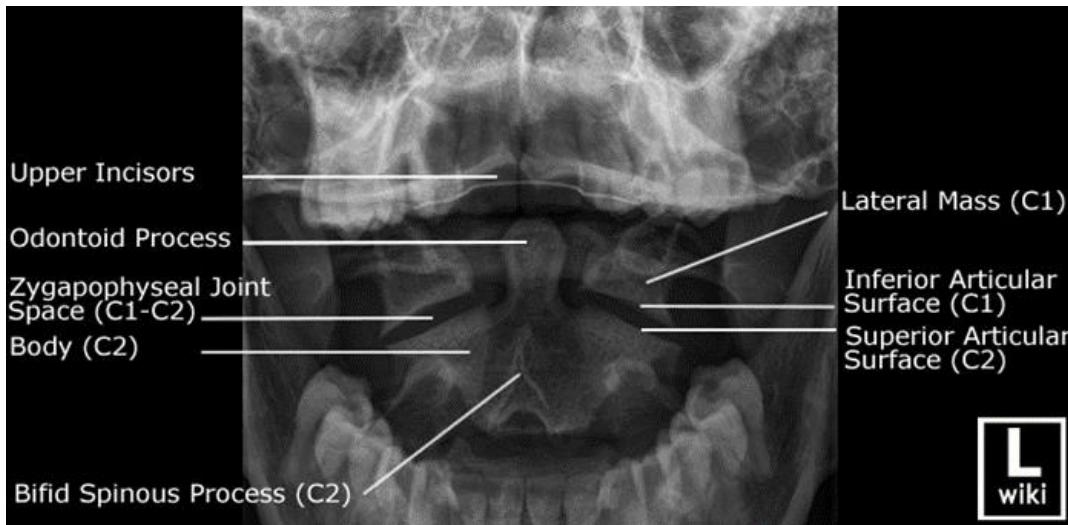

C-Spine X-ray

- Views:

- Lateral View: Must show C1 down to the C7-T1 junction.

- AP View.

- Odontoid (Open Mouth) View: Used to visualize C1 and C2 (especially the dens).

- Pathology:

- Odontoid Fracture (C2): Seen on the open mouth view.

- C2 Fracture (Hangmanโs fracture) can be seen on the lateral view.